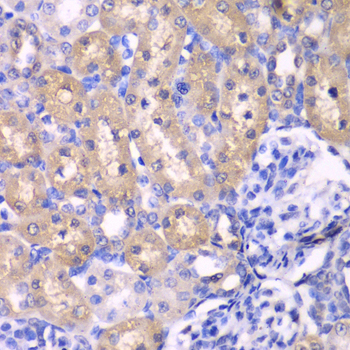

• A2190: image 2

Immunohistochemistry of paraffin-embedded rat kidney using RPS6KB1 antibody at dilution of 1:100 (400x lens).